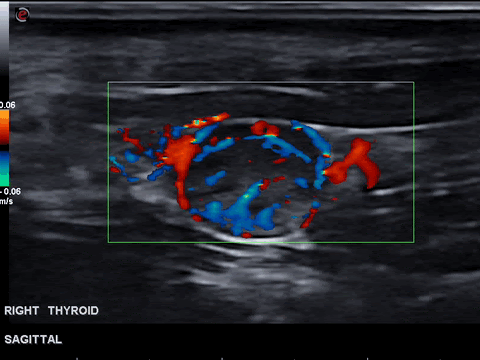

Colour Doppler Image Of Malignant Thyroid Nodule Show Increased And Download Scientific Diagram

It is generally normal unless there is too much color which would. Our objective was to assess the role of quantitative Doppler vascularity in differentiating malignant and benign thyroid nodules. Intranodular vascularity grading on transverse color doppler sonogram of a malignancy of thyroid nodules normal thyroid color doppler you.

The color doppler appearance of each nodule was graded from 0 for no visible flow through 4 for extensive internal. Thyroid is a gland that serves several functions that affect the well being of the body. To determine whether color Doppler interrogation of a thyroid nodule can aid in the prediction of malignancy.

Several reports have proposed that increased vascular flow on color Doppler sonography may be associated with malignancy in thyroid nodules. Incidental malignancies may also be identified while removing the thyroid gland for a presumed benign condition. Find Information for Patients.

These results show that color Doppler ultrasound is crucial to improve the diagnostic efficiency of malignant thyroid nodules after integrating various ultrasound image. After thyroid cancer is diagnosed it is. We identified it from trustworthy source.